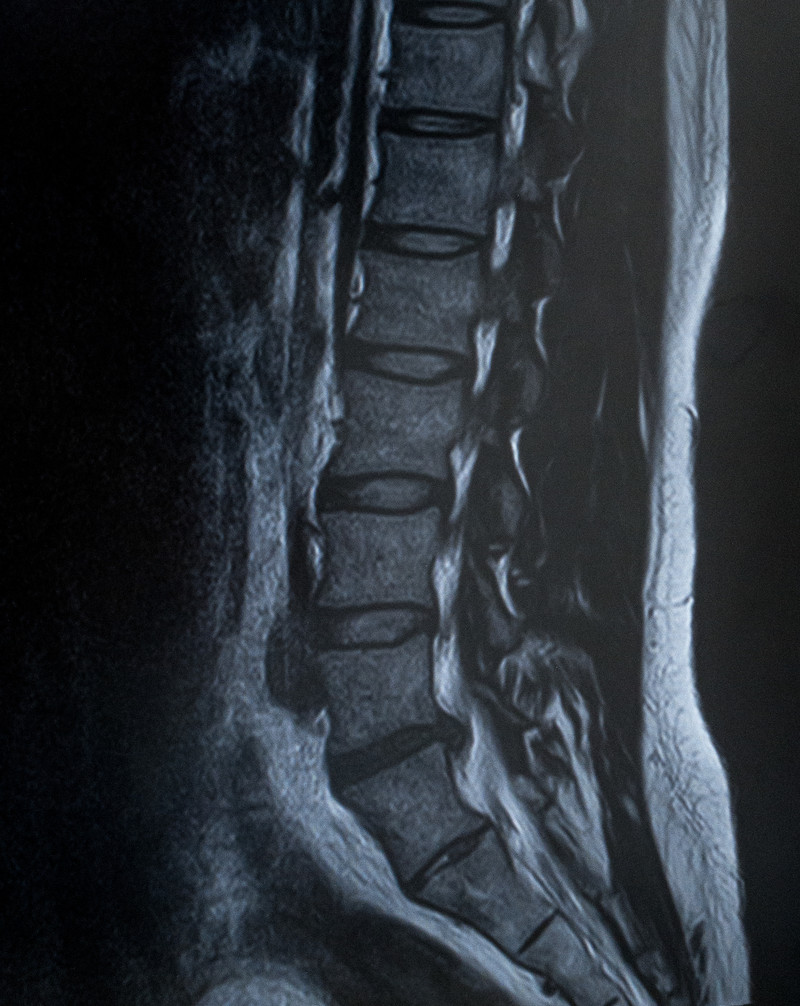

脊柱管狭窄症(せきちゅうかんきょうさくしょう)

椎間板ヘルニア(ついかんばんへるにあ)

腰椎の4番と5番の間の椎間板ヘルニアを模した模型

①レントゲン、CT、MRI等の画像のみに頼った判断

レントゲンやMRI等の画像には何も映らない

ですが病院ではレントゲンやMRI等の画像に頼った判断になるケースが多く、画像上に少しでも

【脊柱管狭窄症や椎間板ヘルニア】らしきものが写っていれば、たとえ

①椎間関節性、②筋・筋膜性、⑥仙腸関節性の影響で痛みやしびれが出ていたとしても

【脊柱管狭窄症や椎間板ヘルニア】になってしまいます。